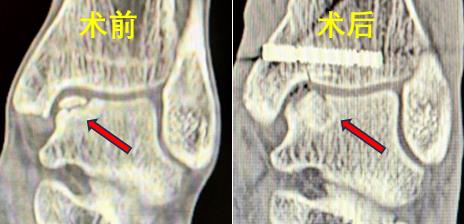

38岁的男性患者蒋某与43岁女性患者潘某,均因踝关节扭伤导致距骨软骨损伤,接受保守治疗后效果不佳,疼痛反复,严重影响日常生活。中南大学湘雅三医院骨科足踝外科团队接诊后,通过详细问诊、体查及影像学检查,明确诊断为 “距骨骨软骨损伤(Hepple III型及V型)”。

手术当日,在麻醉科团队的密切配合下,张克祥副主任医师带领手术团队先通过关节镜彻底清理踝关节内增生滑膜及疤痕组织,再使用3D打印导板于内踝截骨,显露软骨损伤区并彻底清理病灶组织;随后,从患者自身髂骨提取带骨膜的骨栓,将其植入距骨软骨损伤处,整个手术过程顺利,患者术中生命体征平稳。术后,在张文秀、喻俊护士长所带领团队的精细化理疗与康复指导下,患者踝关节疼痛症状显著缓解,目前已逐步进行功能锻炼,患者对治疗效果非常满意。